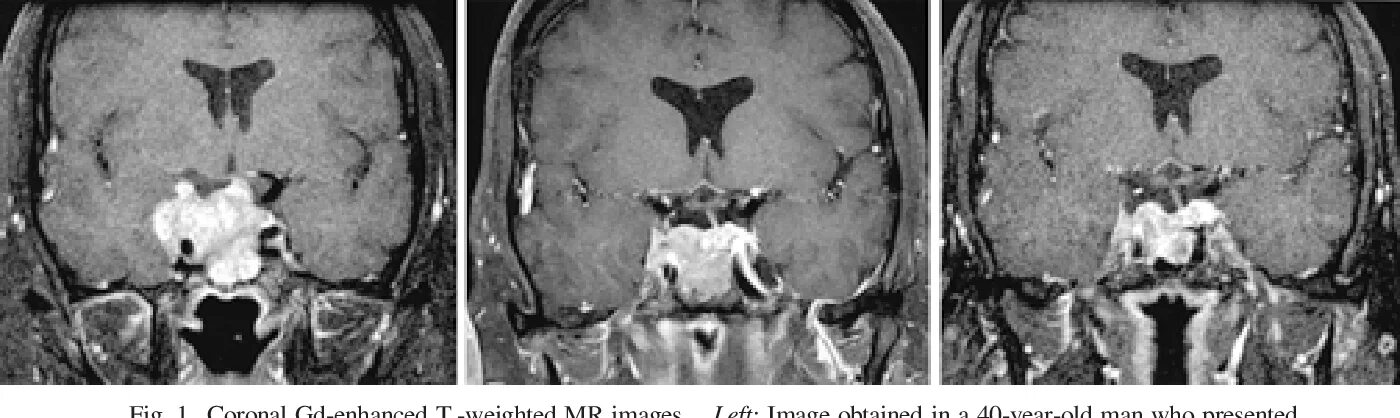

Макроаденома гипофиза